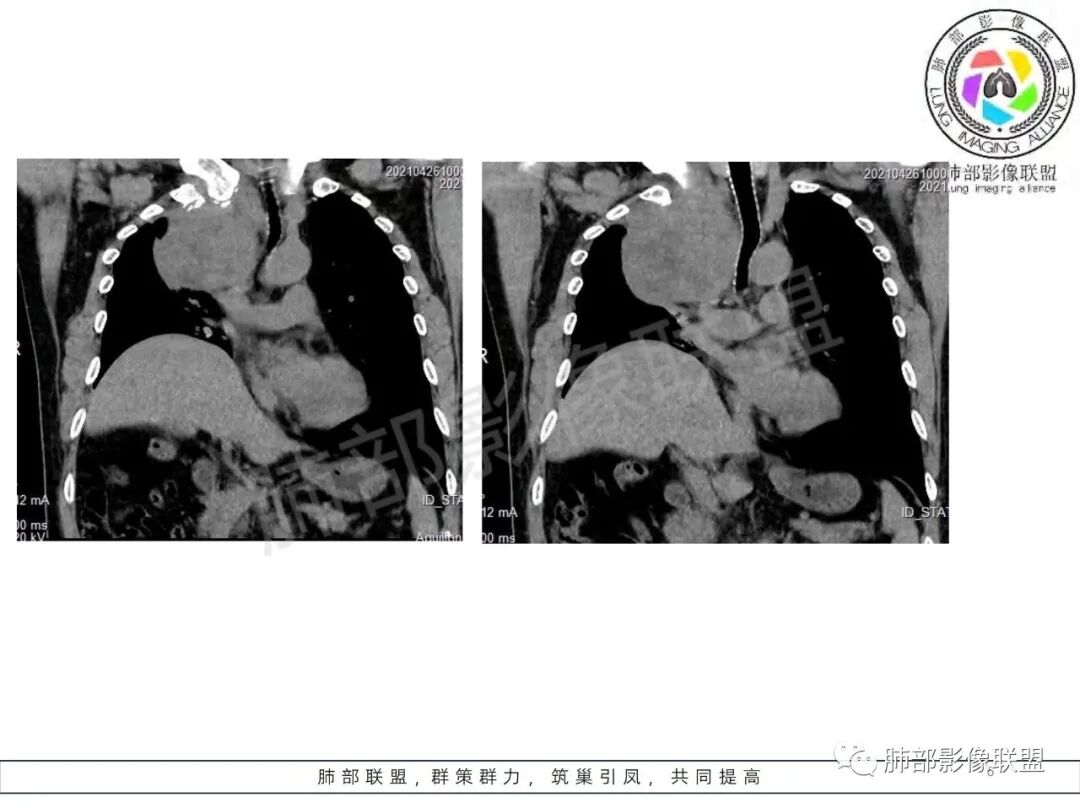

定位肺外,来源于胸膜的SFT(蛇纹状血管)、鞘瘤(不均匀强化,囊变坏死多)、间质瘤(部分层面与食管分界不清)。

肿块把上腔静脉向前部推移,对肺内血管以及气管以推移为主,占位未见肺部血管供血,胸膜掀起处胸膜下脂肪间隙增宽,说明定位在肺外 SFT多为脏层胸膜起源,少部分壁层胸膜起源,壁层胸膜起源SFT不除外,但是胸膜掀起处胸膜下脂肪间隙增宽了,感觉SFT可能性比较小,这样囊变 AB区 纵膈神经起源的神经鞘瘤需要重点考虑,因为CT给的层不够,看不到肿瘤与椎间孔的关系,不敢确定,曾经病理提示高度考虑叶间起源肿瘤,肿瘤细胞呈短梭形细胞构成 不知道和神经鞘瘤是否符合!我重点考虑神经鞘瘤

边界清楚、光滑,D字征,与肺血管、支气管关系不密切,胸膜被掀起都提示肺外来源

胸膜来源:孤立,大的边界清,首选SFT

纵隔:上腔静脉后方主要是膈神经,神经源性可以;后方局部与食道关系密切,食道来源肿瘤也可能,一般食道来源向前推移,这里推移方向不支持;气管受压,壁完整,软骨连续,气管单纯受压没有破坏,后方向内推移,不支持气管来源

粗大强化血管,主要看他起源,如果是来源肺动脉,肺内血管供血一是肺内二是脏层胸膜,肺内排除,只剩脏层胸膜SFT;如果这个是纵隔供血,那它可能是神经源性或者壁层胸膜,也可以是SFT比较少

从影像分析:SFT、神经鞘瘤鉴别可能大